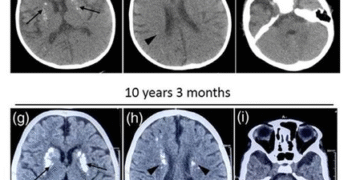

ਖੋਜ ਇੱਕ 11 ਸਾਲ ਦੀ ਕੁੜੀ ਨਾਲ ਸ਼ੁਰੂ ਕੀਤੀ ਗਈ ਸੀ ਜਿਸਨੇ ਬਚਪਨ ਤੋਂ ਹੀ ਲੱਛਣਾਂ ਦਾ ਅਨੁਭਵ ਕਰਨਾ ਸ਼ੁਰੂ ਕਰ ਦਿੱਤਾ ਸੀ, ਜਿਸ ਵਿੱਚ ਬੁਖ਼ਾਰ ਵਾਲੇ ਐਨਸੇਫੈਲੋਪੈਥੀ ਦੇ ਵਾਰ-ਵਾਰ ਐਪੀਸੋਡ ਸ਼ਾਮਲ ਹਨ, ਯਾਨੀ ਕਿ, ਬੁਖਾਰ ਨਾਲ ਜੁੜੀ ਬੇਹੋਸ਼ੀ, ਦੌਰੇ, ਦੇਰੀ ਨਾਲ ਵਿਕਾਸ, ਅਤੇ ਇੱਕ ਛੋਟਾ ਸਿਰ ਦਾ ਆਕਾਰ। ਸਾਲਾਂ ਦੌਰਾਨ, ਉਸਦੇ ਸਕੈਨਾਂ ਨੇ ਦਿਮਾਗ ਦੇ ਵੱਖ-ਵੱਖ ਹਿੱਸਿਆਂ ਵਿੱਚ ਵਧਦੇ ਕੈਲਸ਼ੀਅਮ ਜਮ੍ਹਾਂ ਨੂੰ ਵੀ ਦਿਖਾਇਆ।